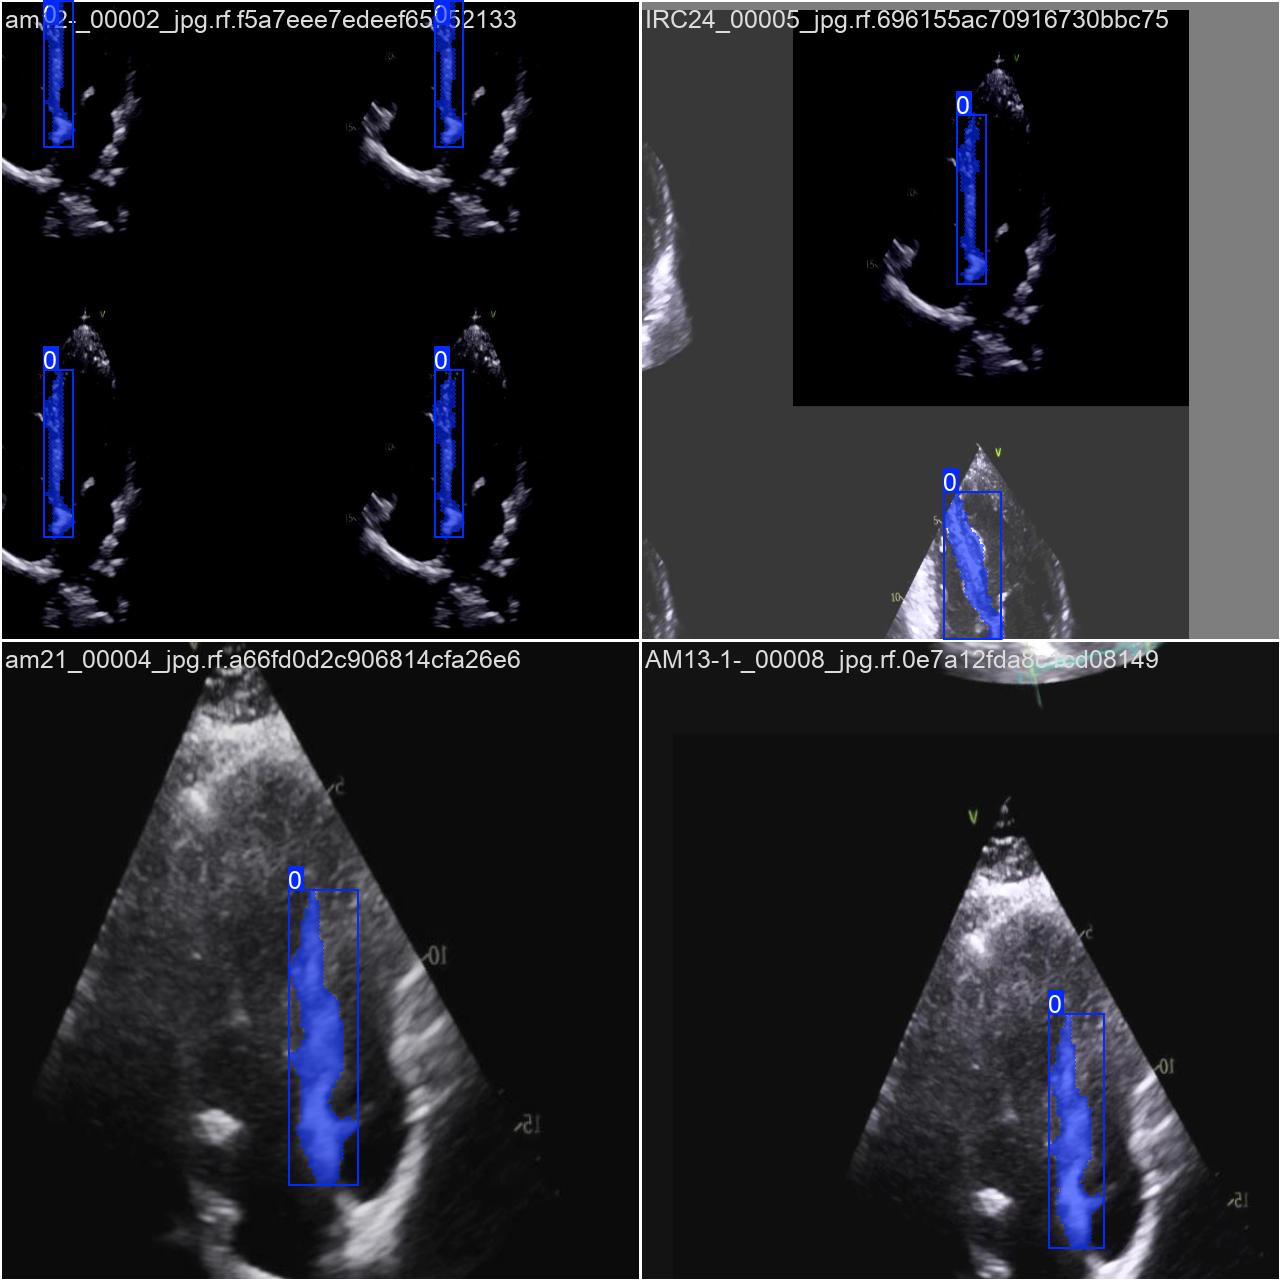

部分数据集图像如下图所示:

部分标注如下图所示: